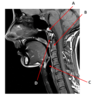

Which structure is labeled by E?

Cricoid cartilage

Which artery is labeled by B?

Maxillary artery

Which nerve is labeled by C?

Inferior alveolar

(Branch of CN V3)

Where in the neck does the common carotid artery split into the internal and external carotid arteries?

At the level of the upper border of the thyroid cartilage

(Around C3/C4)

Which structure is labeled by B?

Mylohyoid